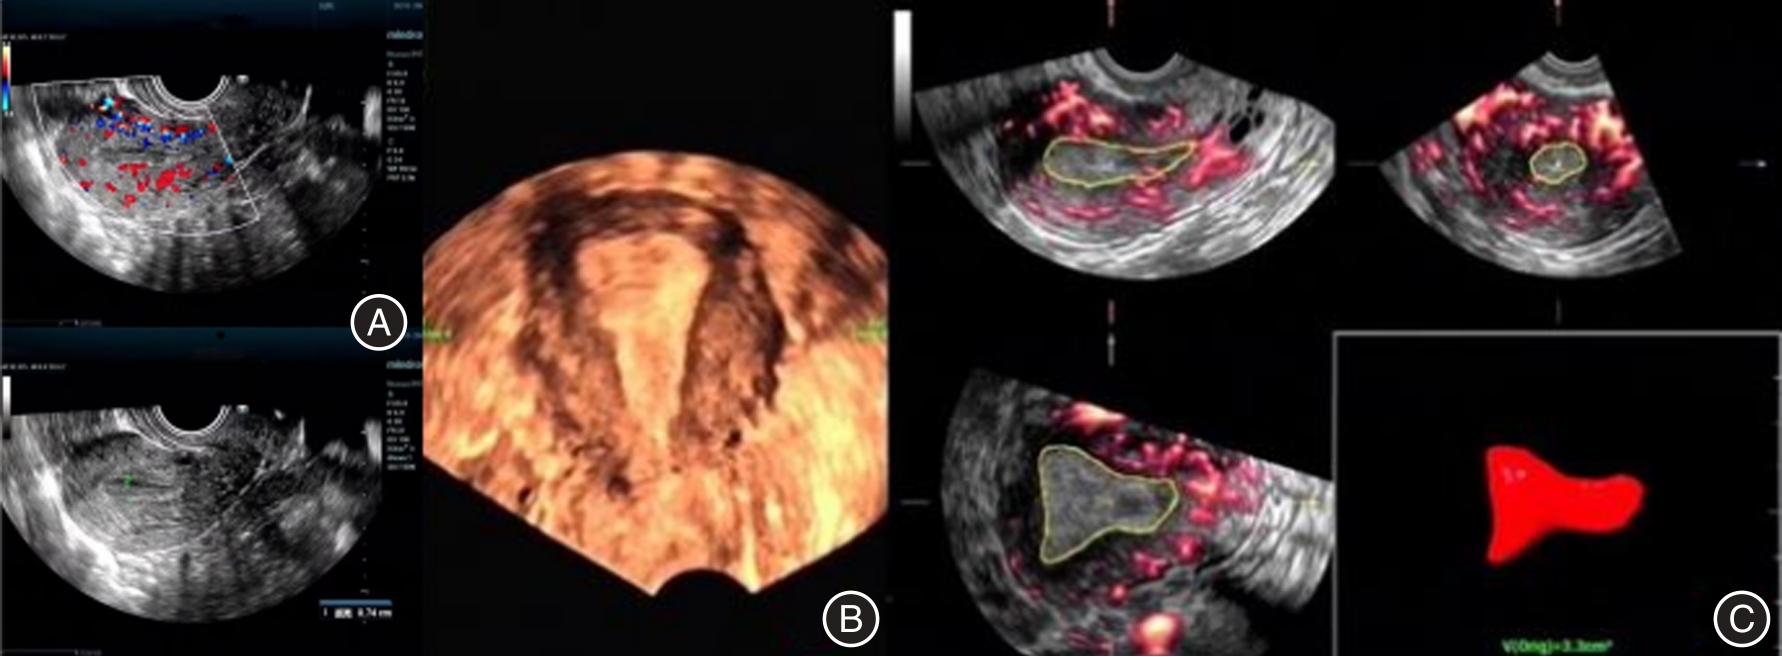

吴新荣,郑颖. 超声多模态评分、血流参数在不明原因复发性自然流产患者体内的变化及联合预测价值[J]. 影像科学与光化学,2021,39(4):538-543. doi:10.7517/issn.1674-0475.201211

焦岩,水旭娟,余彩茶,等. 超声多模态评分在复发性自然流产患者子宫内膜容受性评价中的应用研究[J]. 中国全科医学,2020,23(3):299-304.